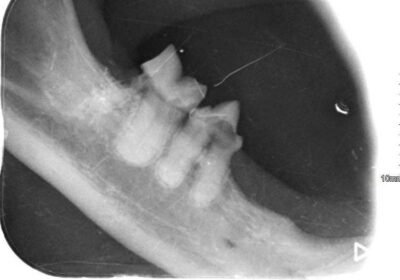

Zaczęło się od trudności z jedzeniem 🍽️, zgłoszonych przez tymczasową mamę, które skłoniły nas do dokładniejszej kontroli. Podczas wizyty weterynaryjnej okazało się, że zęby Loli wymagają pilnej interwencji. Została więc skierowana na zabieg stomatologiczny 🦷, w trakcie którego wykonano RTG jamy ustnej. Badanie wykazało sporo zmian – aż 8 zębów musiało zostać usuniętych.